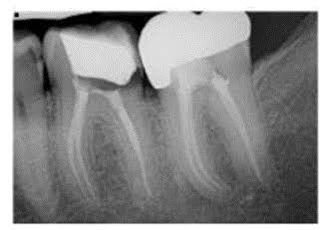

When you have a problem with your teeth, your dentist will first do a visual examination to give you the answers you’re seeking. But a visual examination doesn’t always give you all the necessary information. That’s where X-rays can be beneficial. They help dentists detect possible decay or diseases that just aren’t visible to the naked eye.

X-rays, also known as radiographs, allow your dentist to see between and inside your teeth. Dental X-rays are important because they give your dentist the whole picture. They help dentists see the condition of your teeth and also the roots, jaw placement, and facial bone composition. They will help your dentist find and treat dental problems before they become too serious or advanced.

The dentist can diagnose or ‘uncover’ gum disease, tooth decay, and other dental conditions early enough with the images.

They aid the dentist to diagnose dental infections. The dentist uses the results from the x-rays to identify symptoms of infections, even before they become evident. This helps treat those conditions as early as possible before they become worse and require advanced treatment.